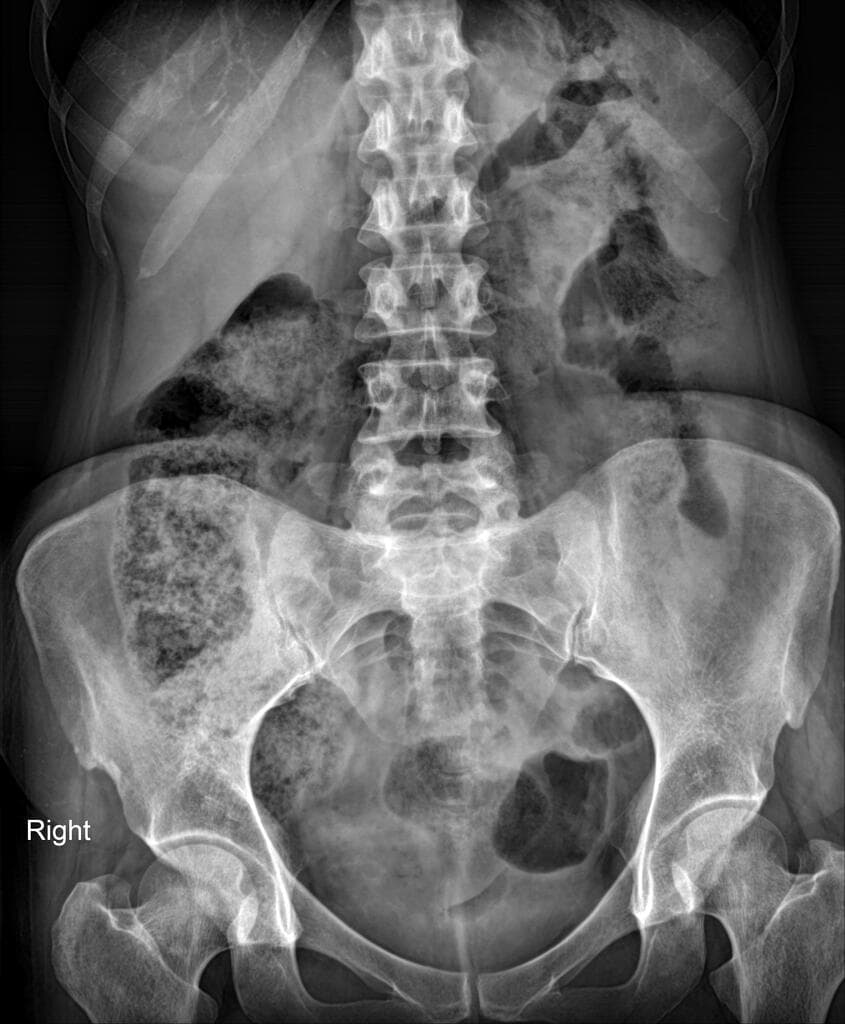

Chụp X-quang bụng không chuẩn bị (CT scanogram) cho thấy hình tăng tỷ trọng (metallic density) tại nửa bụng phải, cụ thể là ống nội soi dạng viên nang bị kẹt (trapped capsule endoscope). Hình ảnh này được xác nhận nằm trong lòng ruột (intraluminal), trong một quai hồi tràng.

Chụp X-quang bụng được thực hiện sau khi làm MRI và CT, xác nhận ống nội soi dạng viên nang bị kẹt tại vùng hạ sườn phải (right hypochondrium).

Hình khí ruột phân bố lệch tâm (eccentric bowel gas pattern), phù hợp với hình ảnh CT.

Các chấm tăng tỷ trọng (punctate radiodensities) đại diện cho barium loãng.

Đường tiết niệu được cản quang sau tiêm thuốc cản quang tĩnh mạch trong CT (opacified renal tract post-CT intravenous contrast administration).